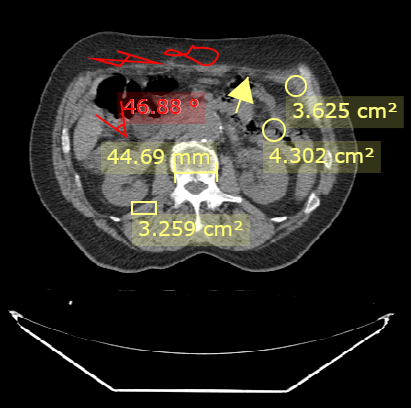

在使用测量与绘制时,DcmViewer默认颜色为黄色。

DcmViewer 基于 Konvajs Shapes 的基础图形开发,并提供以下的测量工具。

点亮按钮,在图像上拖动图标,即可画出所选按钮的形状及测量数据。 再次点击该按钮,取消点亮来取消绘制测量。

选中所画出的的形状,可以通过拖动来改变形状的大小及位置来调整测量。

选中所画出的的形状,将形状拖至X处,或按下delete键可以删除该形状。

测量与绘制只发生在当前的视图上,当使用影像导航至上一张或者下一张影像,再次返回,画出的形状及测量数据不会被清除。